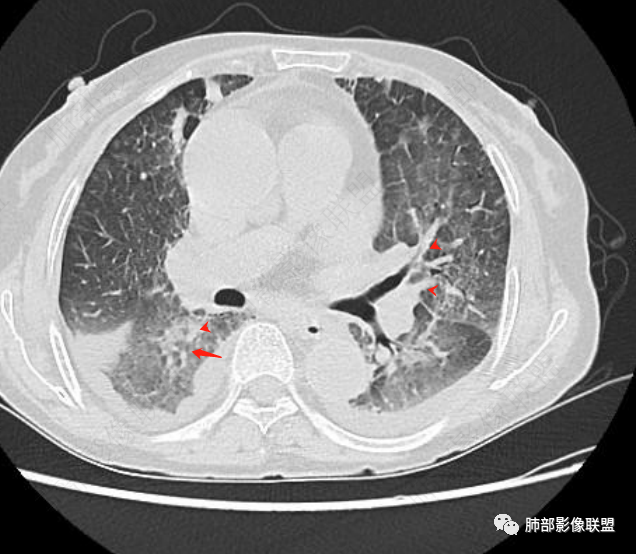

两肺叶后肋膈角区见多发蜂窝状结构破坏表现,双肺叶小叶间隔增厚,左肺上叶后段及舌段和右肺中叶胸膜炎性肉芽肿特点,双侧胸腔少量积液,有类风湿性关节炎治疗史,结缔组织相关性间质性肺病。

发热,有类风湿性关节炎、糖尿病基础病,长期口服激素及免疫抑制剂,双肺多发磨玻璃影及小叶间隔增厚,蜂窝影,支气管扩张考虑非特异性间质性肺炎存在,左肺上叶不规则结节影,周围长毛刺局部肺气肿,考虑慢性炎症,结合pct及crp升高考虑细菌感染,另真菌g升高考虑结合宿主因素,真菌感染需要积极排除。

老年,外阴溃疡加发热,感染指标明显有异常,血气分析,过度呼吸及低氧血症,宿主因素,糖尿病和激素,基础疾病RA。影像,双下肺体积有缩小,有蜂窝?双肺磨玻璃,多发结节,双侧胸水。树芽不明确。是否有旧片,这个患者有UIP背景,是否感染或者UIP急性加重,或者基础上合并肺栓塞及肺水肿?长期激素,没有提供CD4细胞亚群,存在2种情况,1,风湿病没有压制住,肺考虑CTD相关性间质改变,压制过猛,结合感染指标,奴卡是有可能的。激素加糖尿病,结核也带排,激素加磨玻璃加G实验阳性,PCP也带排,临床信息太少,进一步排查

老年女性,有高血压糖尿病及类风湿性关节炎病史,发病前发烧。影像学两肺弥漫性磨玻璃影及斑片影,有渗出性病变亦有间质性改变,支气管血管束增粗,有牵拉扭曲有小气管扩张及间质增厚,两肺下叶胸膜下少许蜂蜜状影。两侧胸腔积液。考虑类风湿性关节炎肺内浸润?合并真菌感染?

老年女性,类风湿关节炎病史多年。发热。以两肺下叶为主弥漫磨玻璃及网格状透亮影,透亮度减低,局部小蜂窝状改变;两肺胸膜下散在几枚实性病灶;双侧胸腔积液。考虑RA-ILDNSIP

两下肺多发蜂窝状表现,双肺小叶间隔增厚,双肺磨玻璃影及部分炎性肉芽肿表现,双侧胸腔积液,有类风湿性关节炎治疗史,结缔组织相关性间质性肺病。患者C反应蛋白和降钙素原都高,是否合并细菌感染

女,71,外阴疼痛2周,发热1周。类风关、高血压、高血糖、卵巢囊肿、肠粘连、胆囊结石等病史及相关药物治疗史。胸部CT:两肺弥漫磨玻璃,血管束增粗,两下肺后肋膈角多发蜂窝,对称分布,双侧胸腔少量积液,纵隔窗心脏大血管影明显增宽。考虑混合性病变,CTD-ILD,并肺水肿?并PJP?。

老年女性,外阴溃疡伴发热,有类风、糖尿病病史,血象及炎症指标高,G试验升高;影像:磨玻璃密度(中央分布为主)胸膜下蜂窝状改变心影增大、两侧胸腔少量积液;小叶间隔增厚,结节;考虑:1.中央分布为主的GGO需考虑:肺水肿、出血、PJP、肺泡蛋白沉着症;2.胸膜下间质性改变蜂窝肺,需考虑UIP、CTD-ILD,综合:两元论:CTD-ILD奴卡,或肺水肿

①影像表现复杂:较弥漫间质性改变,对称磨玻璃密度为主,小叶间隔增厚,有一定重力分布趋势,未见明显纤维化,气囊及蜂窝位于肺边缘,未见典型“月弓征”。心脏影增大,双侧胸腔积液。

这即可见于间质性肺病,也可见于真菌感染(如PJP)、病毒感染,类风湿,以及肺水肿等等。

一般而言,如存在磨玻璃密度影浑浊,有重力分布趋势,肺表面蜂窝影,胸腔积液等等,并不常见于单纯PJP,除非其他因素叠加。

患者存在肺水肿应当是合理的解释。其他旁证还有,心脏影增大,肾小球滤过率降低,双侧胸腔积液等等……

上肺斑片影、结节影,夹杂纤维条索影,边界清楚,新旧不等,胸膜牵拉明显等等,符合较典型继发性肺结核表现,但它却未必是此次就医主要责任病原体!